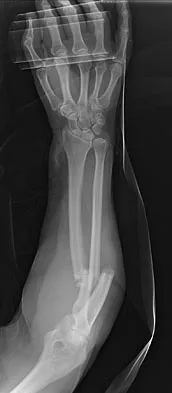

A 33-year-old man reports an enlarging painful soft-tissue mass in his right forearm. A radiograph and MRI scans are shown in Figures 45a through 45c. Treatment should consist of